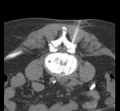

Under computer tomographic or magnetic resonance imaging control, drugs are injected with millimeter precision into the neuralgic points of the spine using fine injection needles. In many patients, this can result in significant pain relief or even freedom from pain. All pain therapy treatments can be carried out on an outpatient basis without any problems due to the low complication rates. A treatment takes a maximum of 10 to 30 minutes.

FacettenblockadeFacet block is a minimally invasive therapeutic procedure for diffuse, motion-dependent non-radicular (not caused by the nerve root) back pain. These complaints are due to wear and tear of the small vertebral joints, caused by wear and tear, poor posture or bending of the spine. These degenerative changes in the small vertebral joints cause approximately 90% of all back pain conditions.

These interventions are CT-assisted, in which a thin special needle is positioned directly on the corresponding nerve plexus (neck, thorax, abdomen, or pelvis) under local anesthesia, and a mixture of local anesthetic and highly concentrated alcohol solution is injected locally. The alcohol solution leads to chemical obliteration of the nerve plexus and thus to pain reduction. The local anesthetic leads to immediate pain reduction when indicated and performed correctly and thus has diagnostic value. For this reason, the procedure is often performed in two stages.